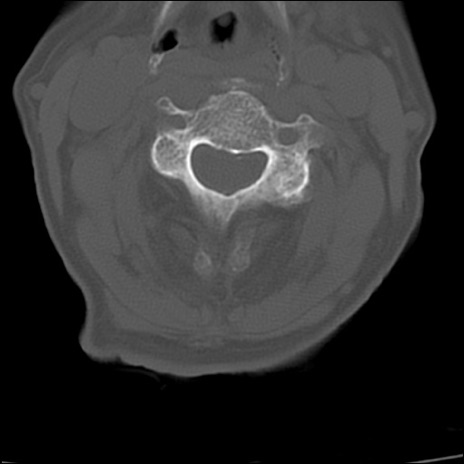

症例48 頚椎CT(横断像)

頚椎CT